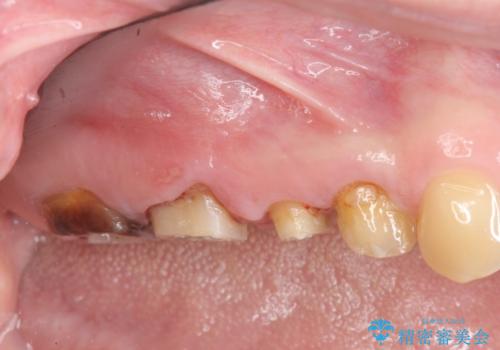

検査の結果、根管・クリアランス・虫歯といった複合的な問題が認められ、以下のような治療計画を進めることとしました。

クラウンの製作スペースの付属 →歯周外科によるスペースの確保

一つ一つの工程を丁寧に行うことで、根尖病変の改善傾向も見られ、安定した歯周環境を整えることができました。